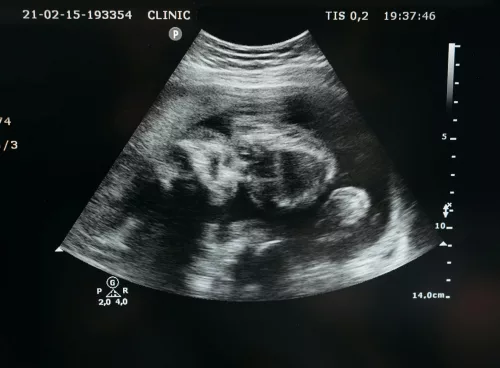

Vanishing Twin Syndrome: The Hidden Story of Lost Siblings in the Womb

Explore Vanishing Twin Syndrome: a common yet mysterious phenomenon where one twin vanishes in the womb. Learn causes,...